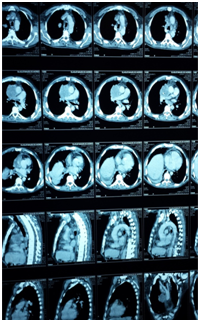

Male 55 years of age, genetic burden to you, dm, heart disease. Tab up to 6 months 5 cigarettes a day for 15 años. PA Starts 4 months myalgia and arthralgia, headache with decubitus, dizziness, dry cough without predominance of time, wheezy, hyperoxia, tired, exhausted, insomnia, lateropulsion, dorsalgia .disfonía ago , dyspnea small efforts, night sweats, back pain, facial edema, lower limb, abominal, upper limb and neck EFTA 90/60, FC 120X MIN, facial edema and neck, even sitting jugular plethora, thoracic venous network, adenomegalia bilateral neck and underarm, edema and abdominal wall members inferiores (Figure 1). He underwent chest CT lung tumor reporting based region right evil-looking, mediastinal tumor with calcifications and data invasion of pericardium and conditioning svcs superior vena cava, mediastinal lymphadenopathy of bilateral hilar groups prevascular (Figure 2) (Figure 3).

Figure 2 Report of CT lung tumor.

Figure 3 Report of CT lung tumor.